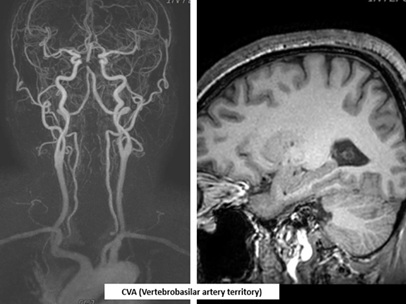

A55-year-old man with previous percutaneous coronary intervention for STEMI, vertebrobasilar infarction, and recent thoracic endovascular aortic repair (TEVAR) for a descending thoracic aortic aneurysm presented to the emergency department with acute chest and back pain without any trauma. He also had hypertension, diabetes, hyperlipidemia, and routinely take the medication. On arrival, his vital signs showed a markedly elevated blood pressure of 178/120 mmHg, while the others within normal limit.